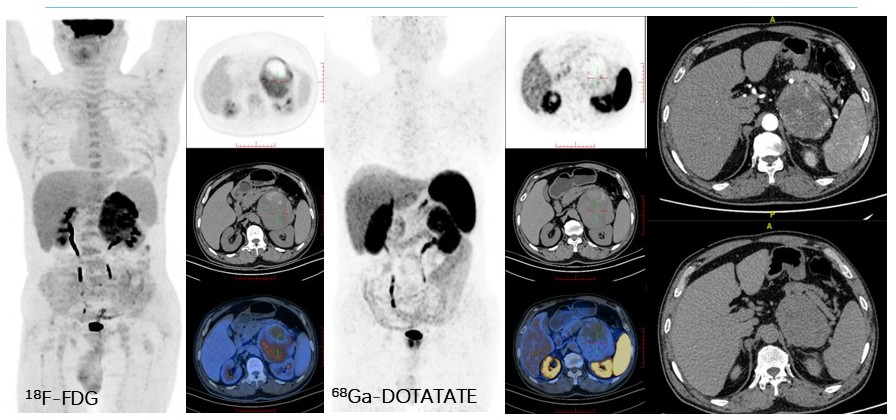

病例(7为一年男性,肾结石检查发现左肾上腺占位,既往高血压病史;实验室检查示脱氢表雄酮水平增高、ACTH水平低;增强CT示左侧肾上腺区肿物伴其内斑片状低密度灶,增强扫描呈明显不均匀强化,病变内见迂曲动脉影;18F-FDG PET/CT示占位内见片状稍高密度灶,代谢不均匀增高68Ga-奥曲肽显像未见明显SSTR高表达;左肾上腺肿物)切除病理为嗜铬细胞瘤

7. 57岁,因肾结石外院行CT发现肾上腺占位2嗜铬细胞瘤